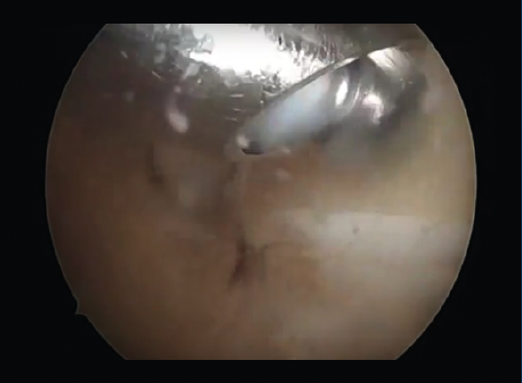

Figura 4. Observación de la cola del astrágalo por artroscopia posterior de tobillo.

En caso de que el tratamiento conservador fracase, se puede proceder a una artroscopia posterior de tobillo (Figura 3), que consistirá en la exéresis de fragmentos óseos (Figura 4), la regularización de la anatomía redundante, la limpieza del FLH, la liberación del retináculo flexor o el inicio del túnel, u otro gesto dirigido a la etiopatogenia del dolor(6).